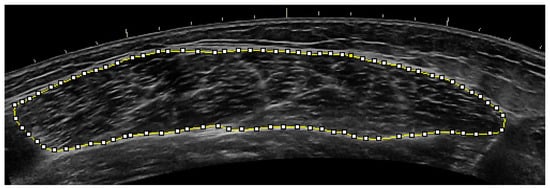

4.3. Ultrasonography Measures ANOVA

- Wagle, J.P.; Carroll, K.M.; Cunanan, A.J.; Taber, C.B.; Wetmore, A.; Bingham, G.E.; Deweese, B.H.; Sato, K.; Stuart, C.A.; Stone, M.H. Comparison of the Relationship between Lying and Standing Ultrasonography Measures of Muscle Morphology with Isometric and Dynamic Force Production Capabilities. Sports 2017, 5, 88. [Google Scholar] [CrossRef]

| Intraclass Correlation (ICC) | 0.99 | 0.99 | 0.99 | 0.99 | 0.98 |

| Lower Confidence Limit | 0.98 | 0.98 | 0.99 | 0.99 | 0.96 |

| Upper Confidence Limit | 1.00 | 1.00 | 1.00 | 1.00 | 0.99 |

| Coefficient of Variation (CV) (%) | 8.70% | 2.67% | 2.67% | 2.18% | 6.33% |

| Group | Variable | Baseline | SE | MS | FOR | Taper |

|---|---|---|---|---|---|---|

| High | CSA (cm2) | 33.0 ± 6.3 | 36.5 ± 6.0 | 36.3 ± 6.8 | 36.1 ± 4.6 | 36.9 ± 3.4 |

| Moderate | CSA (cm2) | 38.9 ± 12.0 | 39.8 ± 10.0 | 42.6 ± 9.8 | 42.7 ± 9.9 | 42.3 ± 9.9 |

| Low | CSA (cm2) | 29.1 ± 6.5 | 30.8 ± 7.0 | 32.1 ± 6.8 | 32.0 ± 5.9 | 33.1 ± 5.3 |

| All Subjects | CSA (cm2) | 32.7 ± 8.6 | 34.7 ± 8.1 # | 36.0 ± 8.4 # | 36.0 ± 7.8 # | 36.3 ± 7.2 # |